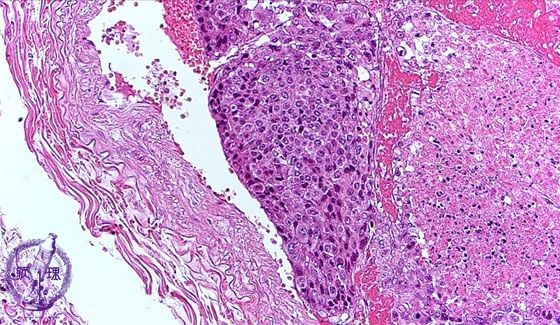

転移性肺腫瘍ミクロ像(HE中拡大)

ミクロ像(HE中拡大):充実性に増生する低分化肝細胞癌が腫瘍塞栓を形成している。腫瘍の右側には壊死が見られる。他の部位では分化度の高い肝細胞癌が見られた。